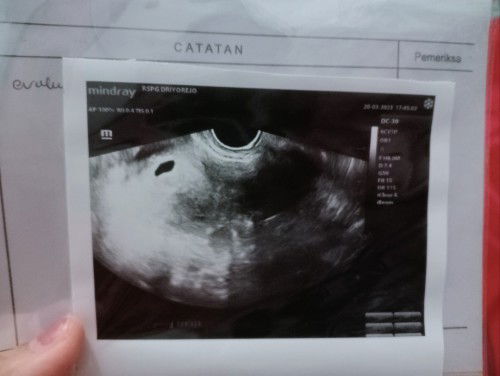

5 week belum ada janin

hamil 5 Minggu tapi masih kelihatan kantung belum ada janin nya, dokter nya suruh balik lagi 2 Minggu lagi, dan kalau dalam 2 Minggu belum ada, ada kemungkinan hamil BO lagi, soalnya bulan September kemarin habis kuret hamil BO, jadi over thinking Bun 🥺🥺